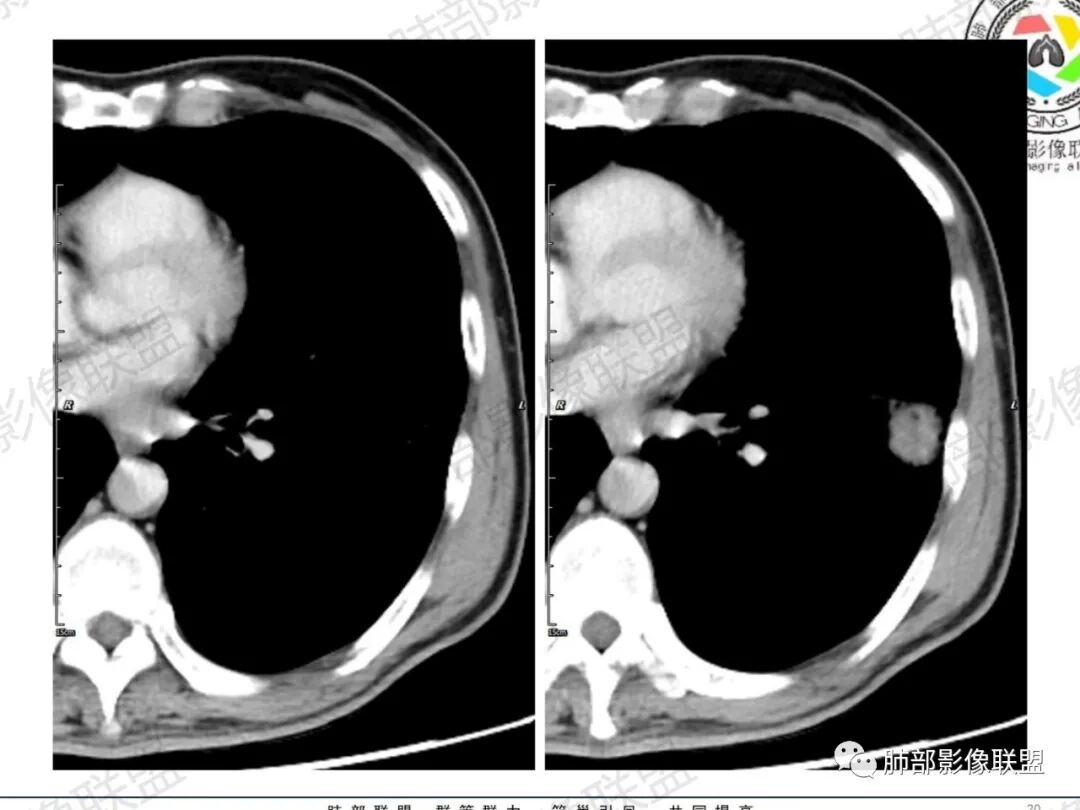

一切∮随缘:左肺下叶不规则肿块,边缘光滑,平直,局部彭隆,分叶,近端支气管堵塞,远端与胸膜相贴,平扫密度尚均匀,增强后不均匀强化,内部可见低密度坏死,胸膜下多发肺气肿,伴双肺散在光滑小结节,实验室肿瘤标志物高,考虑恶性:神经内分泌癌(大细胞),腺癌,鳞癌。

琦遇:恶性没有问题,肺气肿底子、病灶分叶、少许毛刺、叶间胸膜凹陷、部分边缘可见清晰的GGO、胸膜牵拉凹陷、局部胸水、近端支气管截断、部分支气管被推移、占位效应明显、强化特点为不均匀强化、内部有少许沼泽样低强化区,强化部分轻中强化为主、余肺可见转移性结节、左肺上叶似为囊腔型腺癌一枚,肿瘤标志物提示非小、神经内分泌,综合分析考虑大神泌、腺癌、腺鳞癌、鳞癌  同时左肺上叶囊腔型腺癌  肺转移

飞鹰行动:中年人,男性,胸疼入院,左肺下叶占位,张力较高,边界可见分叶,局部可见明显收缩性改变,增强病灶内部有延迟强化表现,考虑恶性病变,大细胞癌伴肺内转移或者囊腔样腺癌伴转移。

蕊:中老年男性,吸烟史,肺气肿背景,左肺上叶类圆形肿块影,边界清晰,边缘凹凸不平,有分叶,支气管进入阻断,临近胸膜栽赃,整体病灶膨隆,局部周围可以清晰ggo,临近叶间裂内凹,轻度强化,并可见多个低密度区,坏死可能,界线不清;肺内多结节,边缘光滑,考虑恶性伴转移,鳞癌、腺癌

傅昌瑜:中老年男性,肺气肿背景,右胸背疼痛1周。CEA、NSE、CYFRA—211升高。左上肺混合磨玻璃结节,内见较多空泡和扩张支气管。左下肺胸膜下肿块,边缘较光滑,深分叶,似有血管进入,与支气管关系不清,内见不均匀强化,见沼泽地样坏死,有胸膜栽赃。另两肺多发圆形小结节。考虑恶性并肺内转移,多原发可能性大,左上肺腺癌,左下肺病理难以判断,小细胞癌?鳞癌?

小锁:中老年男性,肺气肿背景,右胸背疼痛1周。CEA、NSE、CYFRA—211升高。左上肺混合磨玻璃结节,边界清楚,内见较多空泡。左下肺肿块,边缘清楚,深分叶,有血管和支气管进入,胸膜凹陷。另两肺多发圆形小结节。考虑双发原位癌,左上肺腺癌,左下肺大神泌或腺鳞癌可能,肺内转移。

蓝天白云:中年男性,肺气肿背景,左肺下叶肿块,边缘膨隆,有分叶,内有湖泊样坏死,有轻中度强化,局部胸膜栽赃,收缩力不强,周围见肺气肿征象。左肺上叶混合磨玻璃影,边界清楚,考虑都是恶性,左上肺iac,左下肺腺鳞癌,或大细胞肺癌可能。两肺多发结节,考虑转移

毛勤香:老年男性,肺气肿背景,左肺下叶肿块,分叶,边缘光滑,土豆块样,细支气管闭塞,增强轻度不均匀强化,似有坏死,左肺另见多发结节,淋巴结未见明显肿大,恶性确定,吸烟史,鳞癌破坏力强,侵袭力差,多原发的一般很少多于3个,故排后,首先考虑神经内分泌癌,局部血管穿行,鉴别淋巴瘤

周太狼:中年男性,吸烟、高血压史,肿瘤指标升高,肺气肿背景下,左肺下叶肿块影,分叶、膨隆、未跨叶裂,支气管截断,不均匀强化。另双肺多发结节及磨玻璃影,左肺上叶混合磨玻璃,内可见多发空泡影。整体考虑恶性,肺癌伴肺内转移,左下肺鳞癌?神经内分泌癌?左肺上叶囊腔腺癌?